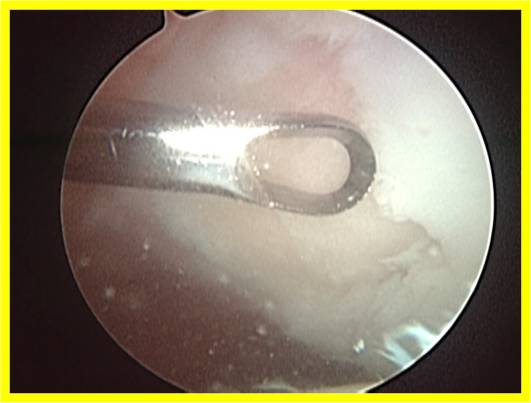

Using 2 tiny holes in front of the knee, the surgeon is able to insert a camera into the joint to carefully access the cartilage damage. The other tiny hole allows the surgeon to introduce the metal awl to perform the microfracture.

This is a video of my patient undergoing microfracture for a patella ulcer: